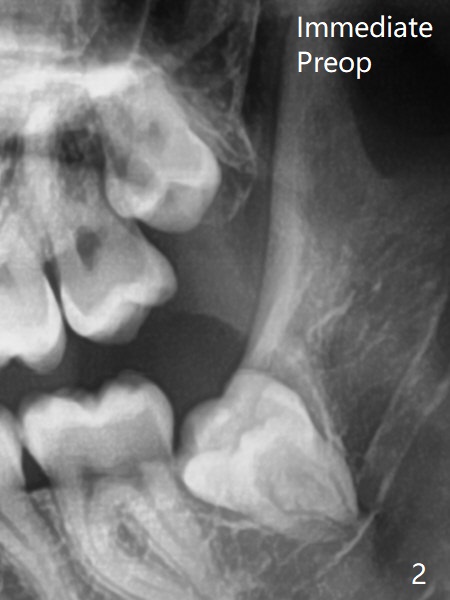

Two years 10 months between Fig.1 and 2.  The chief complaint is mastication pain of the upper 3rd molars, as related to the thin gingiva upon incision.  Overlapping and crowding are much more severe as seen intraop than X-ray indicates.